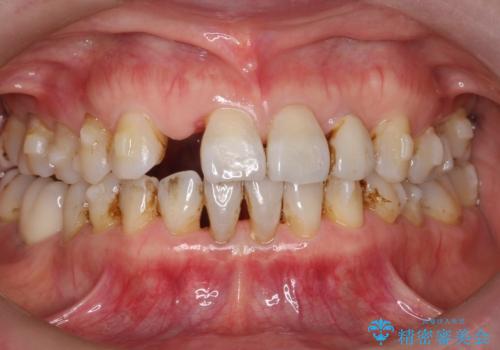

- 前歯の隙間が気になるというお悩みで当院にご相談にいらっしゃいました。長年、この隙間が気になっていたようです。

アライナー矯正とインプラント治療を組み合わせることで、見た目の美しさだけでなく、噛み合わせのバランスも改善できるとの治療計画を立てました。

前歯に隙間がありましたが、とても綺麗に並びました。患者様にも喜んでいただけました。

前歯に隙間ができた原因として、舌の癖がありました。そのため、舌の癖を治す口腔筋機能療法(MFT)も行いました。